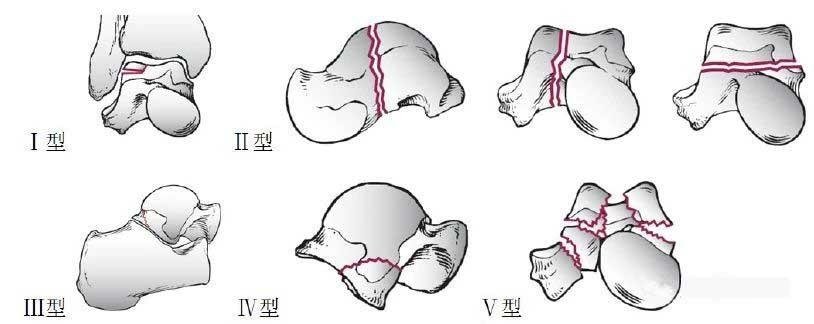

Otro método de clasificación y el más aceptado es la clasificación de Sneppen propuesta por Sneppen et al., Christensen y Baumgaertner, que se divide en 5 tipos según el lugar y la gravedad de la fractura:

Tipo I: fractura transcartílago de la superficie articular del astrágalo troclear;

Tipo Ⅱ: fracturas en el plano coronal, sagital u horizontal del cuerpo del astrágalo. La probabilidad de necrosis en pacientes sin luxación del cuerpo del astrágalo es aproximadamente del 25%, y la luxación combinada puede llegar al 50%;

Tipo Ⅲ: fractura cifótica del astrágalo;

Tipo Ⅳ: Fractura de la apófisis lateral del cuerpo del astrágalo;

Tipo V: fractura comprimida y conminuta del cuerpo del astrágalo, con tasa de necrosis de fractura extremadamente alta y mal pronóstico.